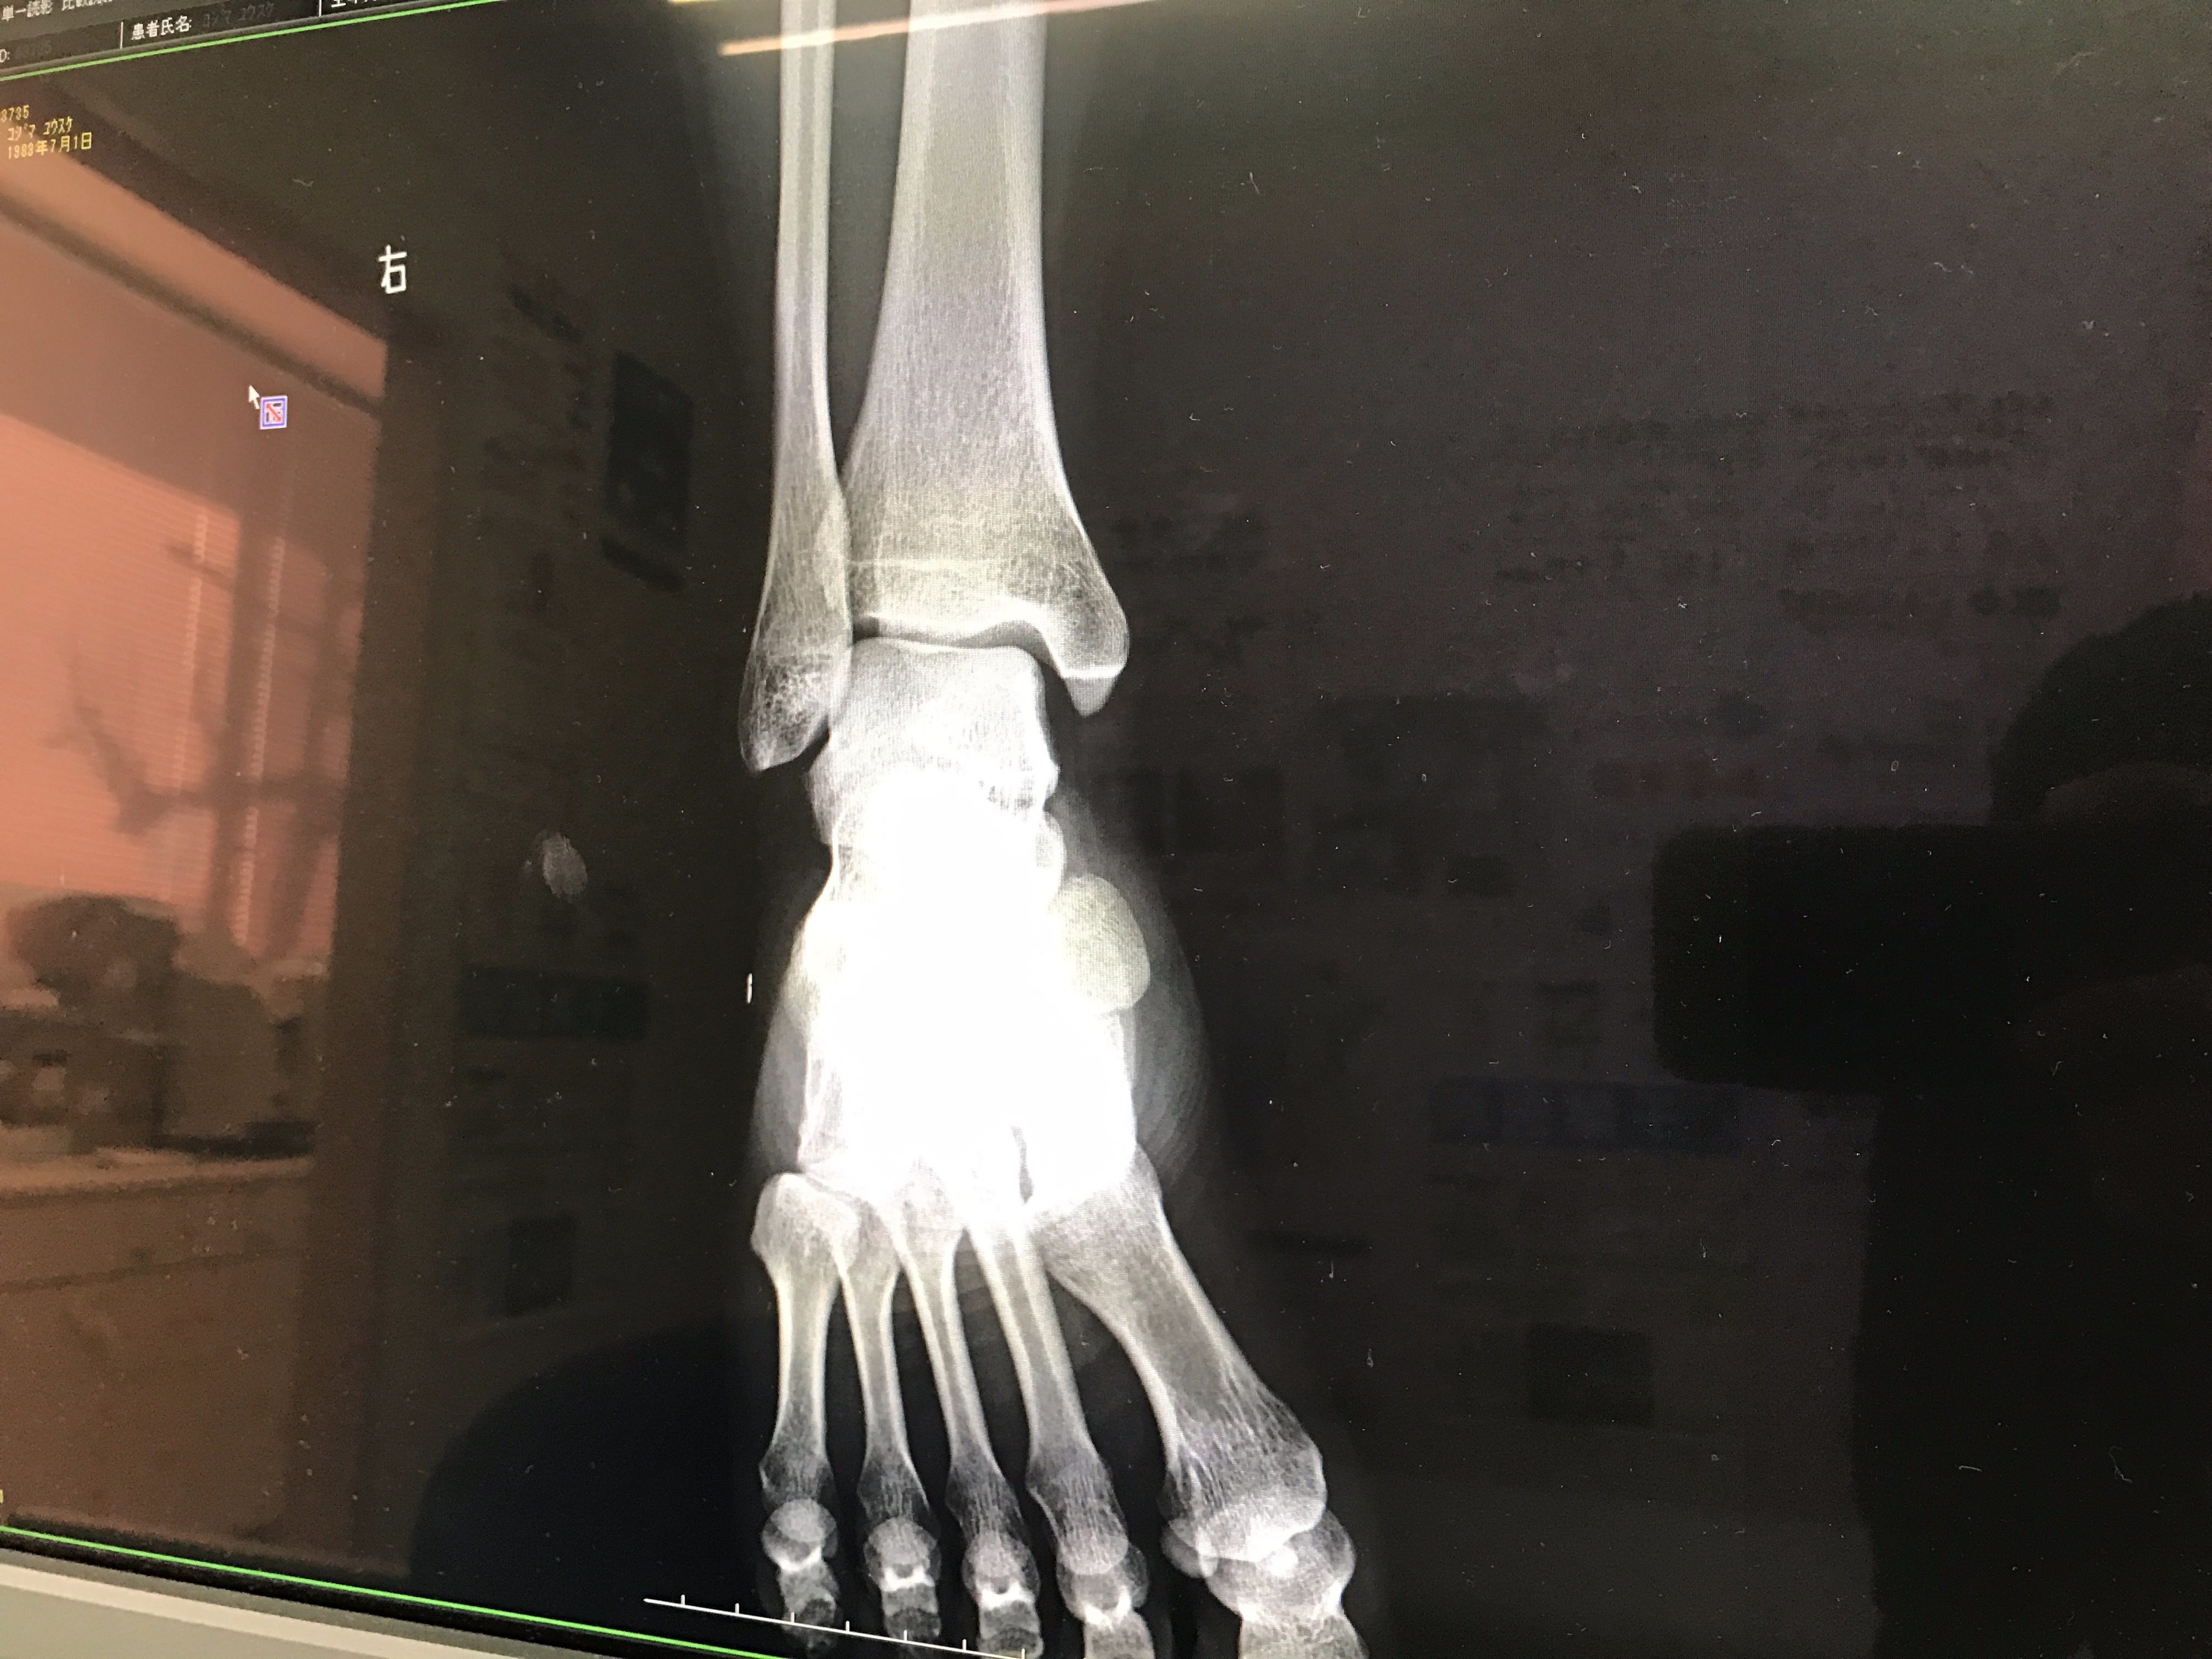

正月休みで溜め込んだカロリーを消費しようとランニングをしたら踵にヒビが入り